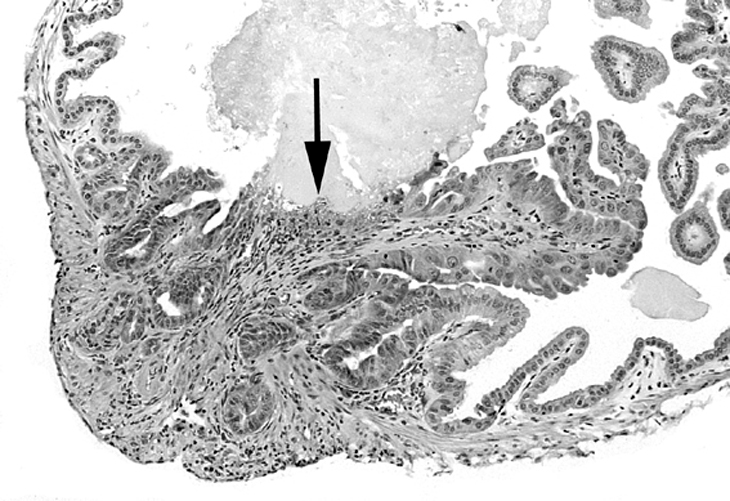

Papillary hyperplasia of the gallbladder with a small mucosal ulcer (arrow).